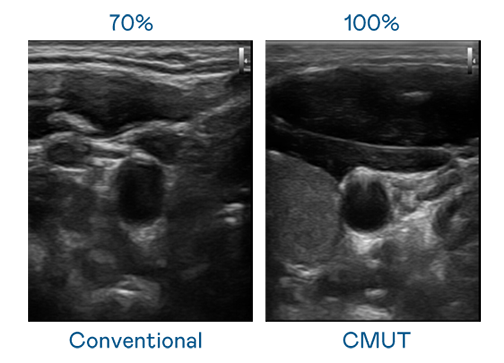

CMUT 技术是一种用电容式微机电元件来产生超音波讯号的技术。与传统 PZT 压电式技术相比,CMUT 频宽增加 30%,更宽频的超音波讯号让影像解析度大幅提升,是实现高影像品质医疗超音波扫描、促进精准医疗发展的关键技术。

超音波影像的解析度高低,首先取决于探头能发出的讯号频宽。z6.com CMUT 可提供高清晰的超音波讯号,提供高频宽、高灵敏度、影像纹理细节更高的超音波影像,协助医护人员缩短影像判读时间及利用精准的医疗影像进行诊断。